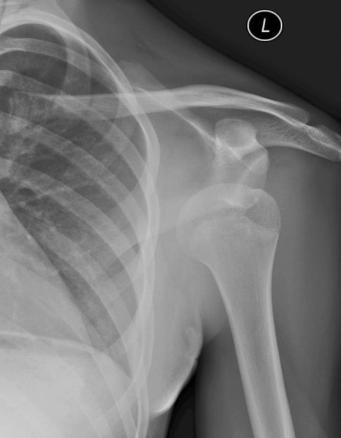

Luxation antérieure gléno-humérale sous-coracoïdienne.

Extrait de : Image mystérieuse n°444